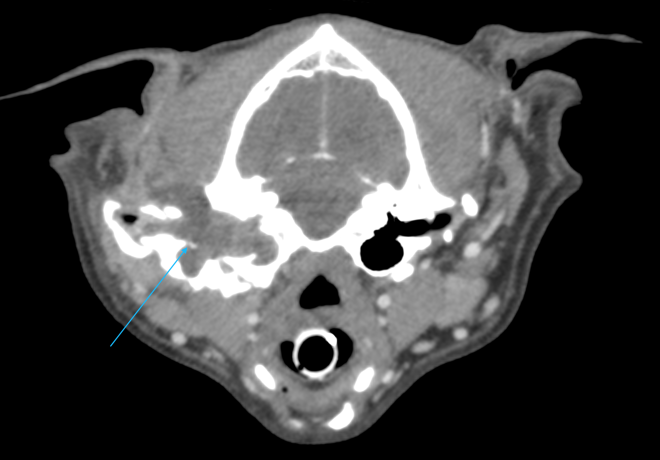

CTでは左耳の耳道、鼓室胞の中に充実性の病変が見られ、耳道の骨は一部融解していました。CTの所見から真珠腫性中耳炎が疑われました。真珠腫は外耳炎などにより鼓膜が破れ、鼓膜の内側の中耳内、鼓室胞に上皮細胞が浸潤することで慢性的に炎症が起こり、痛みや神経症状、開口障害といった症状が出ます。